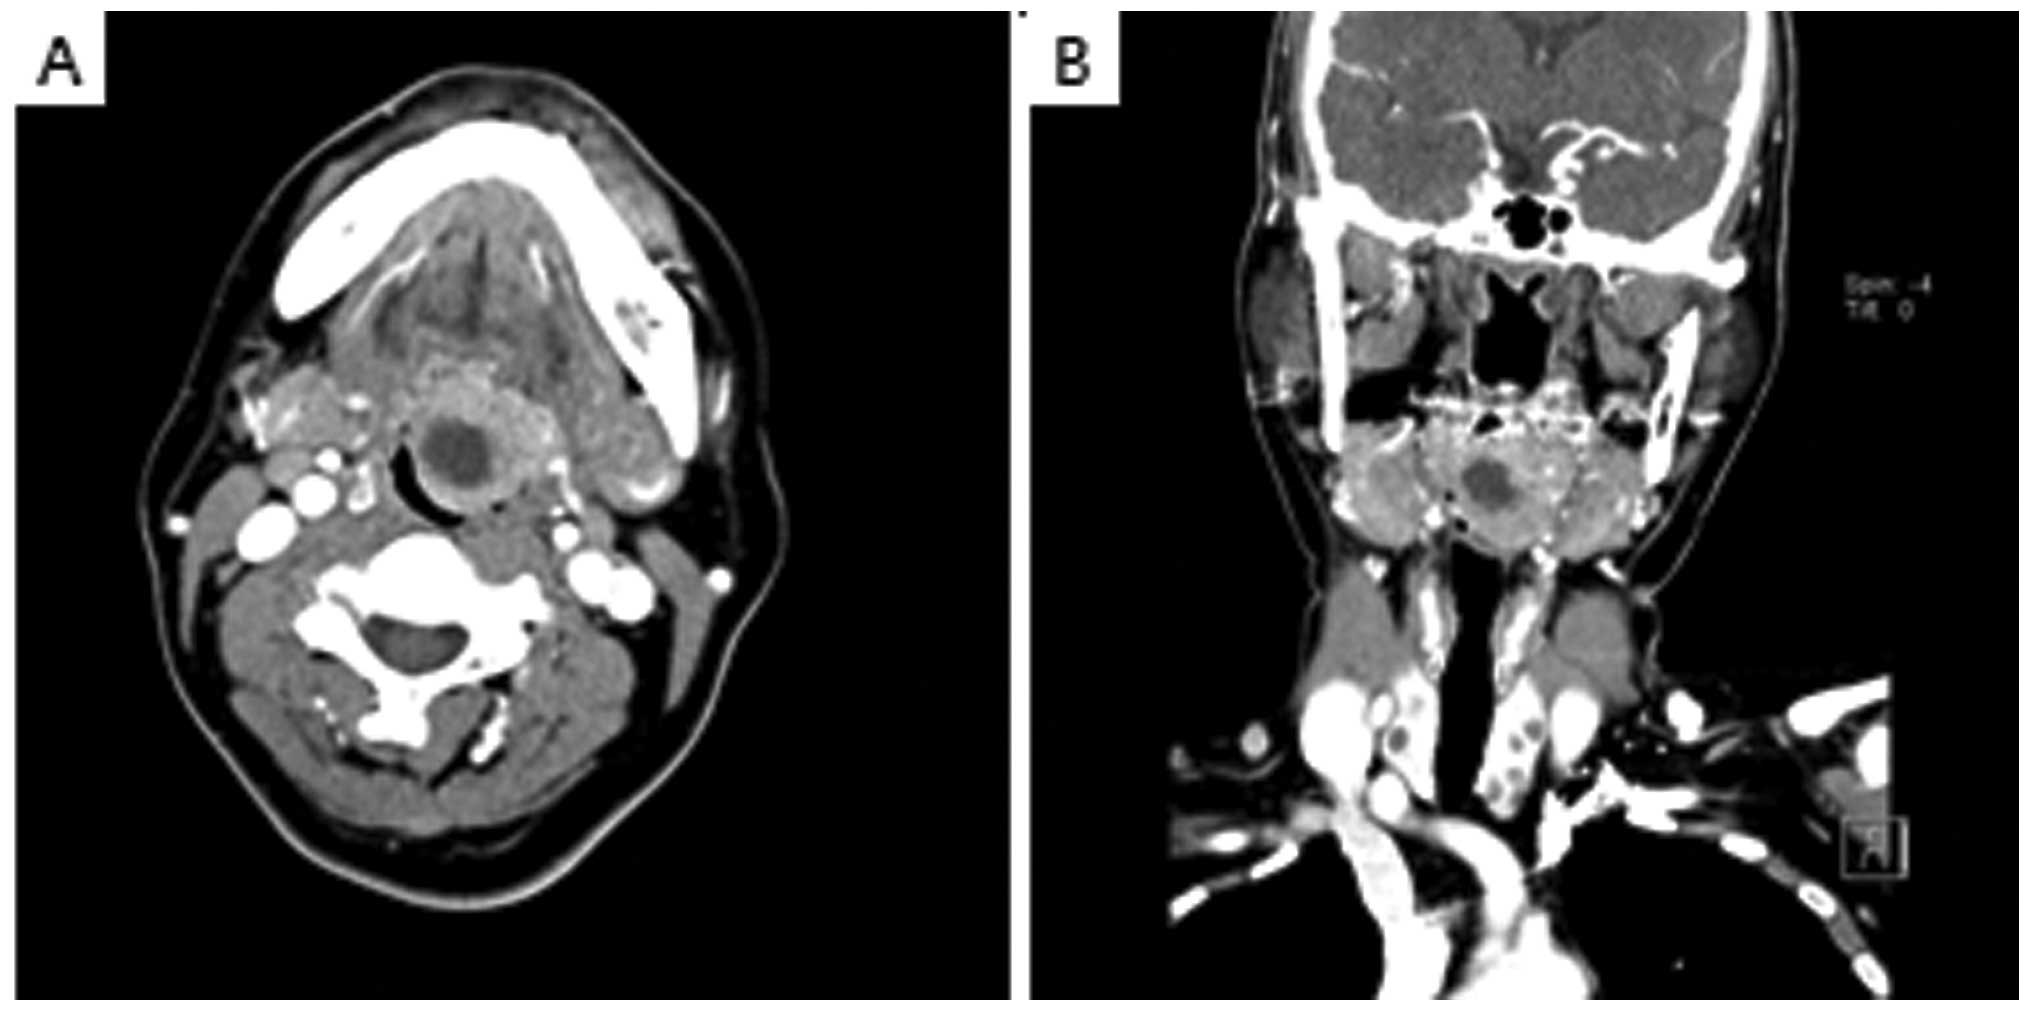

A 52-year-old female visited Chosun University Hospital (Gwangju, Korea) complaining of the sensation of foreign bodies in the pharynx that had developed several months previously. The patient’s history and family history were unremarkable. Upon physical examination, a mass 3×3 cm in size, with an unclear boundary and no associated ulcer, was discovered on the left side of the tongue base (Fig. 1). No other significant findings in the nasal cavity or the neck area were observed. The results of the general blood tests were normal. Computed tomography (CT) revealed necrosis in the central area of the left side of the tongue base and a 2.9×2.6 cm circular lesion showing contrast enhancement was also detected (Fig. 2). As several colloidal cysts were detected in both thyroids, ultrasonography was performed. The results were clinically insignificant.

Figure 2.

Results of (A) axial and (B) coronal CT scans with contrast enhancement. An enhanced mass approximately 2.9×2.6 cm in size with internal necrotic low density on the left side of the tongue base is visible.